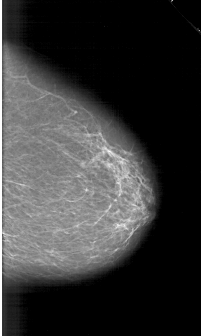

A_1164_1.RIGHT_MLO

RIGHT_MLO LINES 6631 PIXELS_PER_LINE 4141 BITS_PER_PIXEL 12 RESOLUTION 43.5 NON_OVERLAY